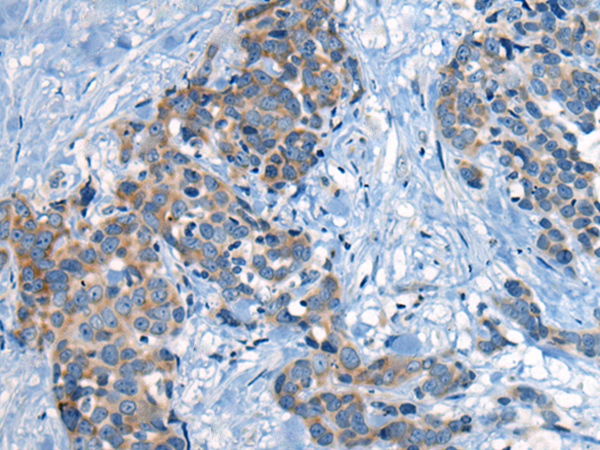

分类: 科研抗体货号: P06279别名:应用: WB,IHC反应种属: Human, Mouse, Rat

分类: 科研抗体货号: P06217别名: NEM7应用: WB,IHC反应种属: Human, Mouse, Rat

分类: 科研抗体货号: P06266别名: NCBP; Sto1; CBP80应用: WB,IHC反应种属: Human, Mouse, Rat

分类: 科研抗体货号: P06210别名:应用: WB,IHC反应种属: Human, Mouse, Rat

分类: 科研抗体货号: P06263别名: CML3; NACED; NAT8-LIKE应用: WB,IHC反应种属: Human, Mouse, Rat

分类: 科研抗体货号: P06205别名: CACC; GOB5; CACC1; CLCRG1; CaCC-1; hCLCA1; hCaCC-1应用: IHC反应种属: Human

分类: 科研抗体货号: P06262别名: DNAS1L2应用: IHC反应种属: Human, Mouse

分类: 科研抗体货号: P06202别名: AMY; CLAC; CLACP; CFEOM5; CLAC-P应用: WB,IHC反应种属: Human, Mouse

分类: 科研抗体货号: P06261别名: DCR2; CD264; TRUNDD; TRAILR4; TRAIL-R4应用: WB,IHC反应种属: Human